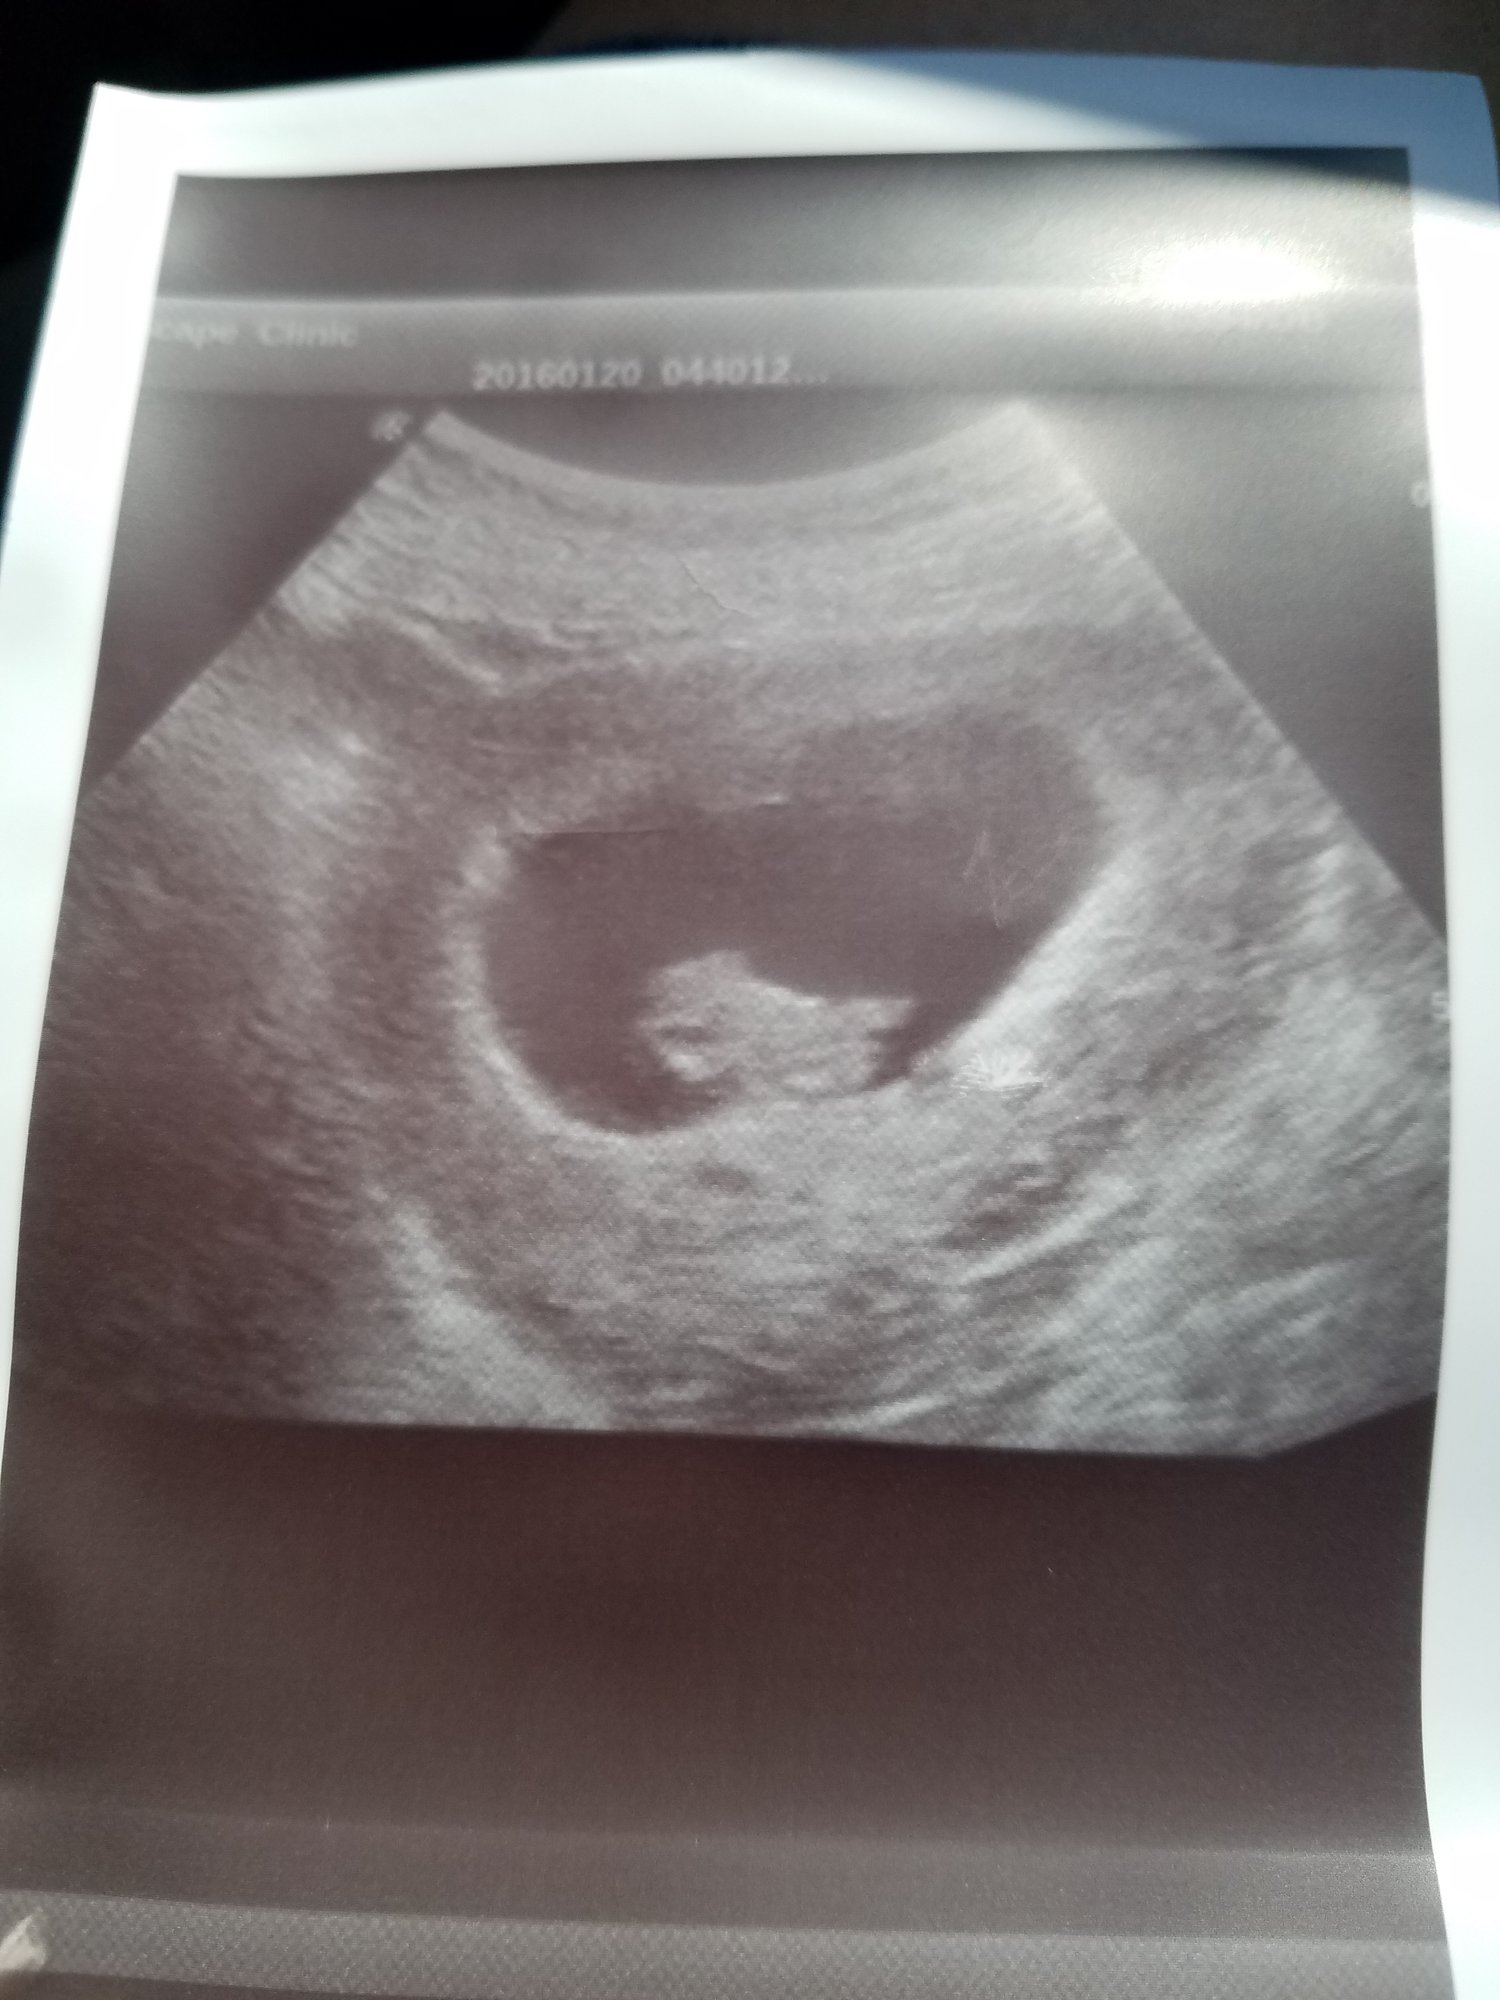

update: since I get to go to the doctor every 1-2 weeks, this is from last Friday.

this is from the high risk obgyn with the better ultrasound machine. good news. she thinks they are monodi but will confirm again in a few weeks

although she is measuring them to be smaller than LMP. by 5-7 days.. due date still in march, ill ask my regular obgyn what she thinks this Friday .

2 little nuggets. good heart rates

147 and 153